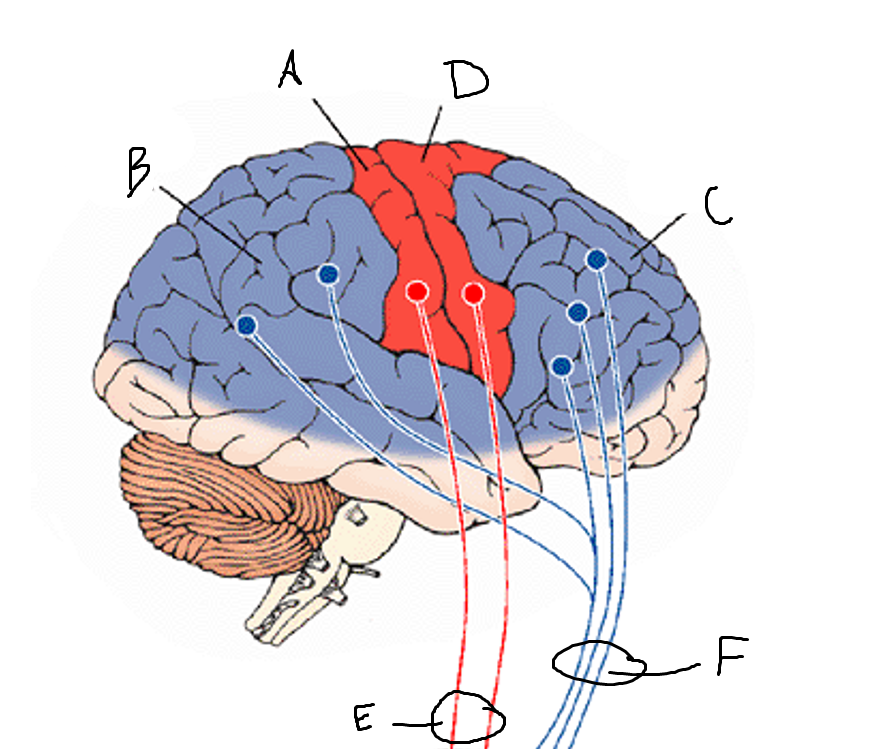

basal ganglia

A

somatosensory cortex

B

parietal association cortex

C

frontal and prefrontal cortices

D

primary motor cortex

E (where are the projections?)

putamen

F (where are the projections?)

caudate